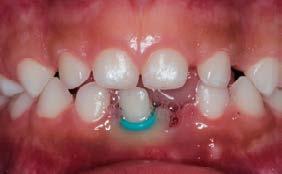

realizó una resonancia magnética de cráneo, que no mostró evidencia de actividad tumoral (Figura 1).

En 2025, la paciente presentó cefalea que posteriormente se localizó en la región maxilar. En consulta externa se realizó la exodoncia del órgano dentario 17 (Figura 2). Debido a la persistencia del dolor y la aparición de una lesión en la tuberosidad maxilar, se llevó a cabo una biopsia, cuyo resultado histopatológico fue compatible con metástasis de carcinoma ductal. Se documentó una lesión sólida de 21 mm que comprometía el hueso maxilar superior derecho, con destrucción ósea e impronta en el seno maxilar. Además, se observó compromiso del espacio graso retromaxilar, así como adoncia del segundo y tercer molar superiores derechos y ganglio submandibular derecho de 11 mm, con características sugestivas de infiltración tumoral (Figura 3).